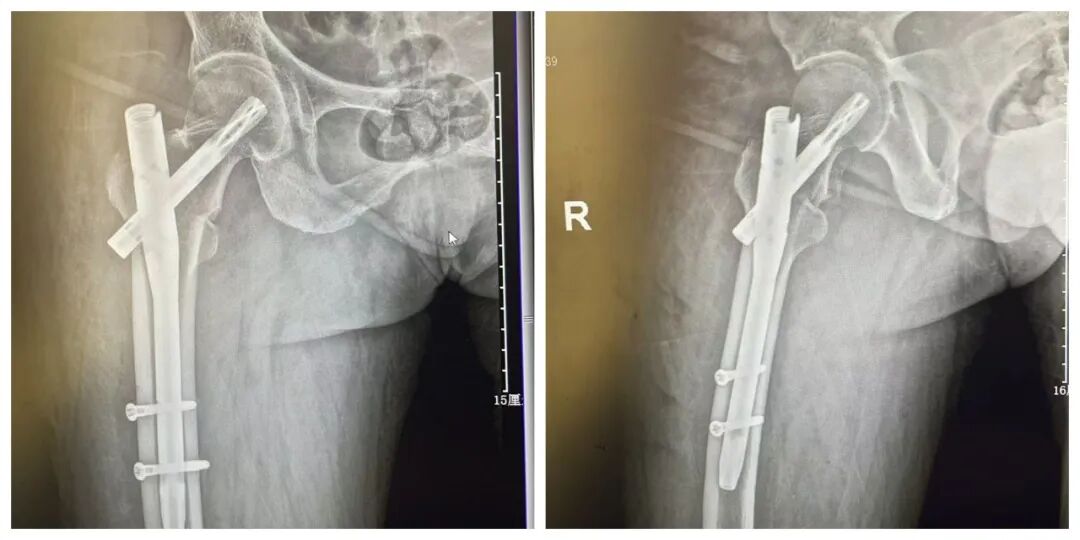

尽管 患者高龄 给手术带来了不小压力,但骨科手术团队凭借精湛医术和丰富经验,顺利完成了手术。术后复查DR,提示 金属内固定在位,断端对位良好。

患者术后影像

手术过程顺利,术后 复查DR ,显示 断端对位良好,金属内固定在位, 手术效果满意。